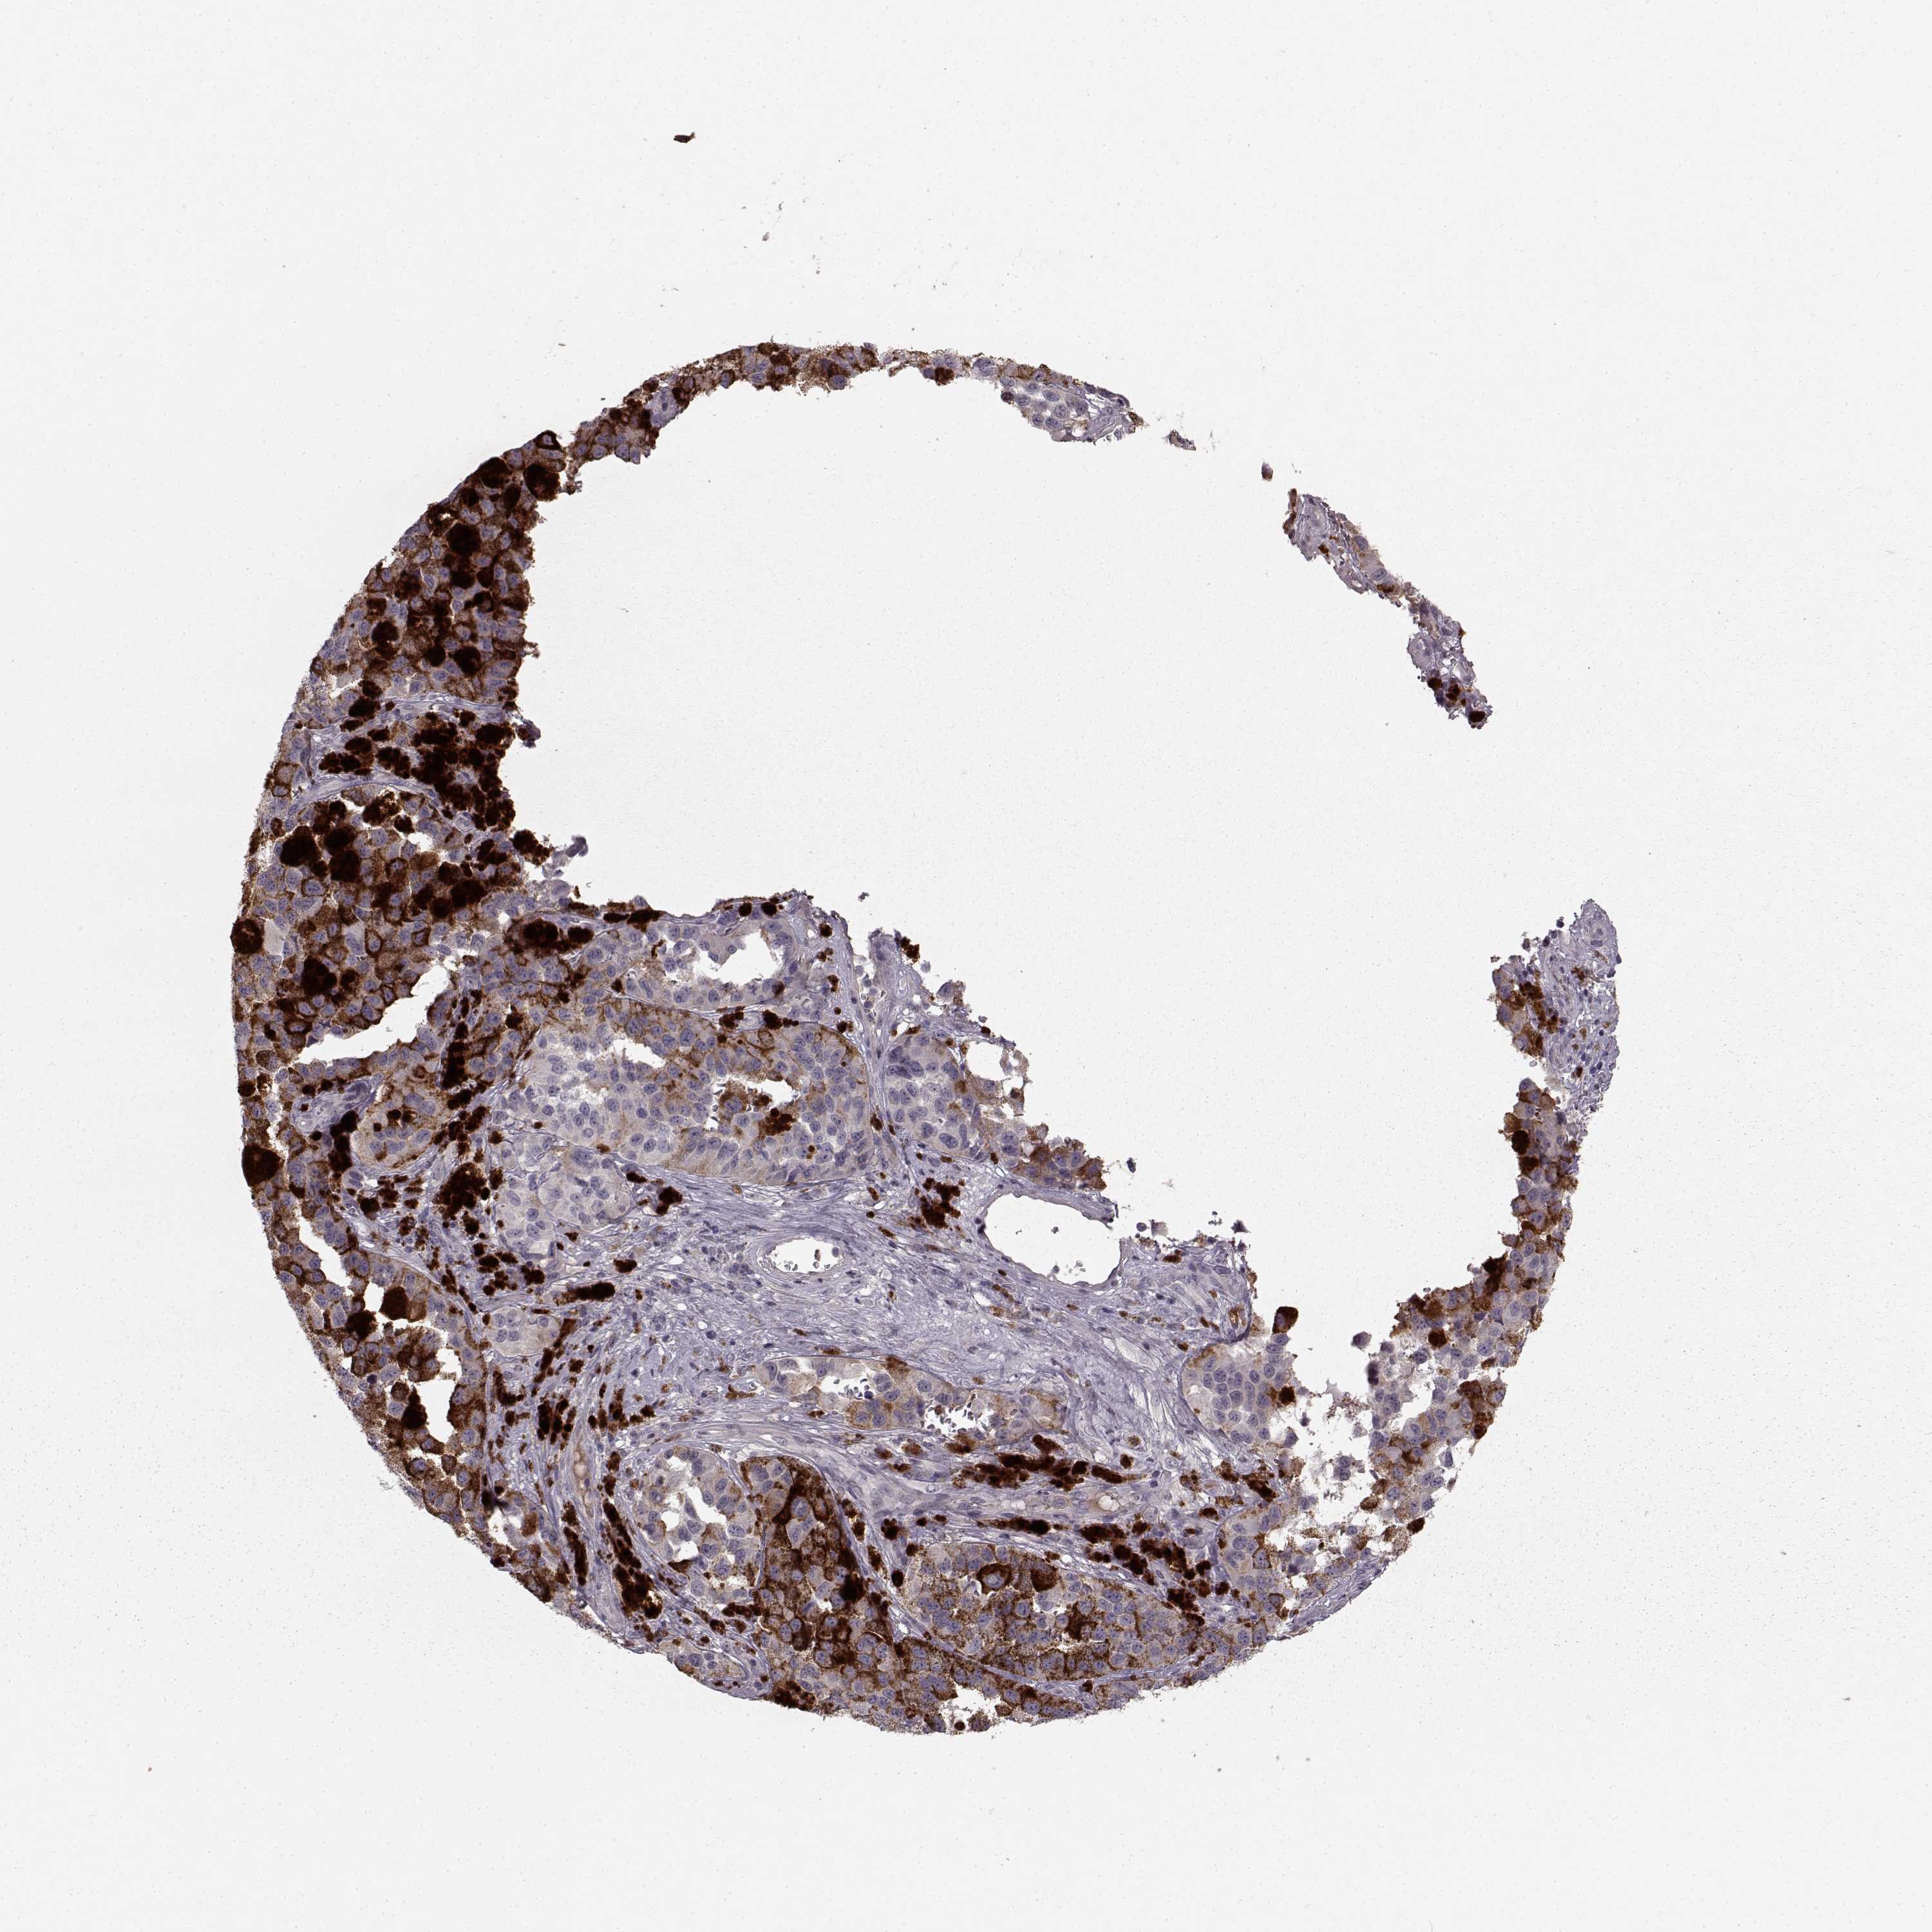

MELANOMA - Protein expressioni

A mouse-over function shows sample information and annotation data. Click on an image to view it in a full screen mode. Samples can be filtered based on level of antibody staining by selecting one or several of the following categories: high, medium, low and not detected. The assay and annotation is described here.

Note that samples used for immunohistochemistry by the Human Protein Atlas do not correspond to samples in the TCGA dataset.

Antibody stainingi

Antibody staining in the annotated cell types in the current human tissue is reported as not detected, low, medium, or high, based on conventional immunohistochemistry profiling in selected tissues. This score is based on the combination of the staining intensity and fraction of stained cells.

Each image is clickable and will lead to virtual microscopy that enables deeper exploration of all samples and also displays staining intensity scores, fraction scores and subcellular localization as well as patient and tissue information for each sample.

Antibody HPA067812

Antibody HPA071461

Staining

High

Medium

Low

Not detected

Intensity

Strong

Moderate

Weak

Negative

Quantity

>75%

75%-25%

<25%

None

Location

Nuclear

Cytoplasmic/membranous

Cytoplasmic/membranous,nuclear

Malignant melanoma, NOS

Malignant melanoma, Metastatic site